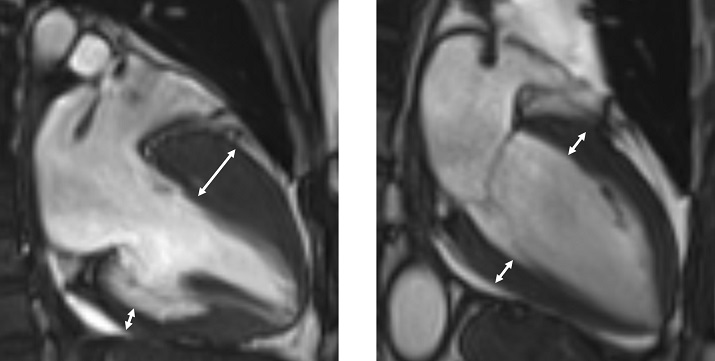

<»çÁøÀÚ·á ¿ÞÂʺÎÅÍ ºñÈļº ½É±Ùº´ÁõÀ» °¡Áø ȯÀÚÀÇ ÀÚ±â°ø¸í¿µ»ó, Á¤»ó ½ÉÀå ÀÚ±â°ø¸í¿µ»ó>

Áø´ÜÀº ½ÉÀåÃÊÀ½ÆÄ, ÀÚ±â°ø¸í¿µ»ó(MRI) µî ¿µ»ó °Ë»ç¸¦ ÅëÇØ ÀÌ·ç¾îÁö¸ç µÎ²¨¿öÁø ½É±Ù ³»ºÎ¿¡ ¼¶À¯È³ª Áö¹æ Á¶Á÷ º¯¼º °°Àº Á¶Á÷ º¯È°¡ °üÂûµÇ±âµµ ÇÕ´Ï´Ù. ÇÏÁö¸¸ Á¶Á÷ º¯¼ºÀÌ ¾ø´Â °æ¿ìµµ ¸¹À¸¹Ç·Î, ¼øÈ¯±â³»°ú Àü¹®ÀÇÀÇ Á¾ÇÕÀûÀÎ ÆÇ´ÜÀÌ ÇʼöÀûÀÌ´Ù.